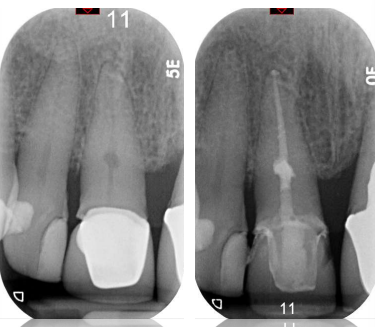

orthograde endodontics only

possible haemorrhage

* Necrotic pulp – black

* Vital pulp – pink

active irrigation

* need to access resorption defect to kill cells to stop process

* CaOh can be useful if not happy with disinfection process then obturate – can use active irrigation

intervisit medicament

thermal obturation